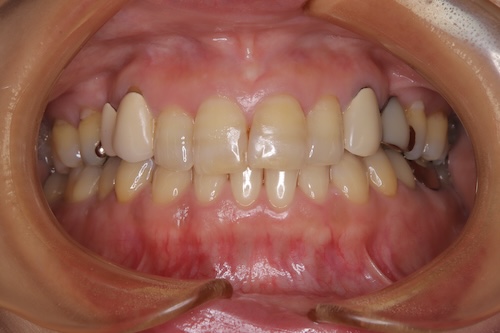

美白を目指した50代女性のホワイトニング経過と成果

50代女性 バンディング歯のお客様。 初診時シェード 右上1D3 右下3A4 目標シェードは040の歯の白さになりたいと来院された。施術内容

- 施術前